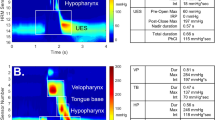

B-mode (2D) ultrasound has also been used to assess lingual propulsion during oral bolus transport. However, it has been more common for M-mode traces, which can represent sequential movements of the tongue dorsum during swallowing as display of linear distance against time, from which quantitative measurements could be made [6]. Peng et al. [7] divided the swallowing process into five phases based on specific inflection points identified on M-mode traces. However, it has been not clearly used in the quantitative assessment of tongue movements.

Ultrasound data were acquired using an Articulate Instruments EchoB system remotely controlled via USB from a personal computer running Articulate Assistant Advanced (AAA) software version 2.16 [8]. The echo return data were recorded at the rate of 54 frames per second (fps) with 127 beam-formed echo pulses evenly spread over a 104° field of view (FOV) providing a resolution of approximately 0.8°, so when the tongue’s surface is 5 cm from the probe, the distance between the scanlines is under 1 mm. The depth setting was 90 mm, and the resolution along each scanline is well below 1 mm. Standard graphical interpolation was performed on the raw data to convert it to an image for analysis in AAA, similar to the image processing that is normally carried out within a dedicated ultrasound scanner. The low-frequency convex transducer frequency operated at 4 MHz. The participant was fitted with a headset to stabilize the ultrasound probe (Fig. 1).

For each frame (i.e., time point), the distance (mm) from the tongue’s surface to the palate was exported, measuring along the radial fan lines (the arrows in Fig. 3).

Tongue Depression Depth

Each frame’s tongue spline contained a depression, or concavity in the tongue’s surface, like a cup. The size of this depression and its location was defined using the greatest radial distance from the location of the hard palate to the visible tongue’s surface (the longest arrow in Fig. 3) as a proxy measure of its depth.